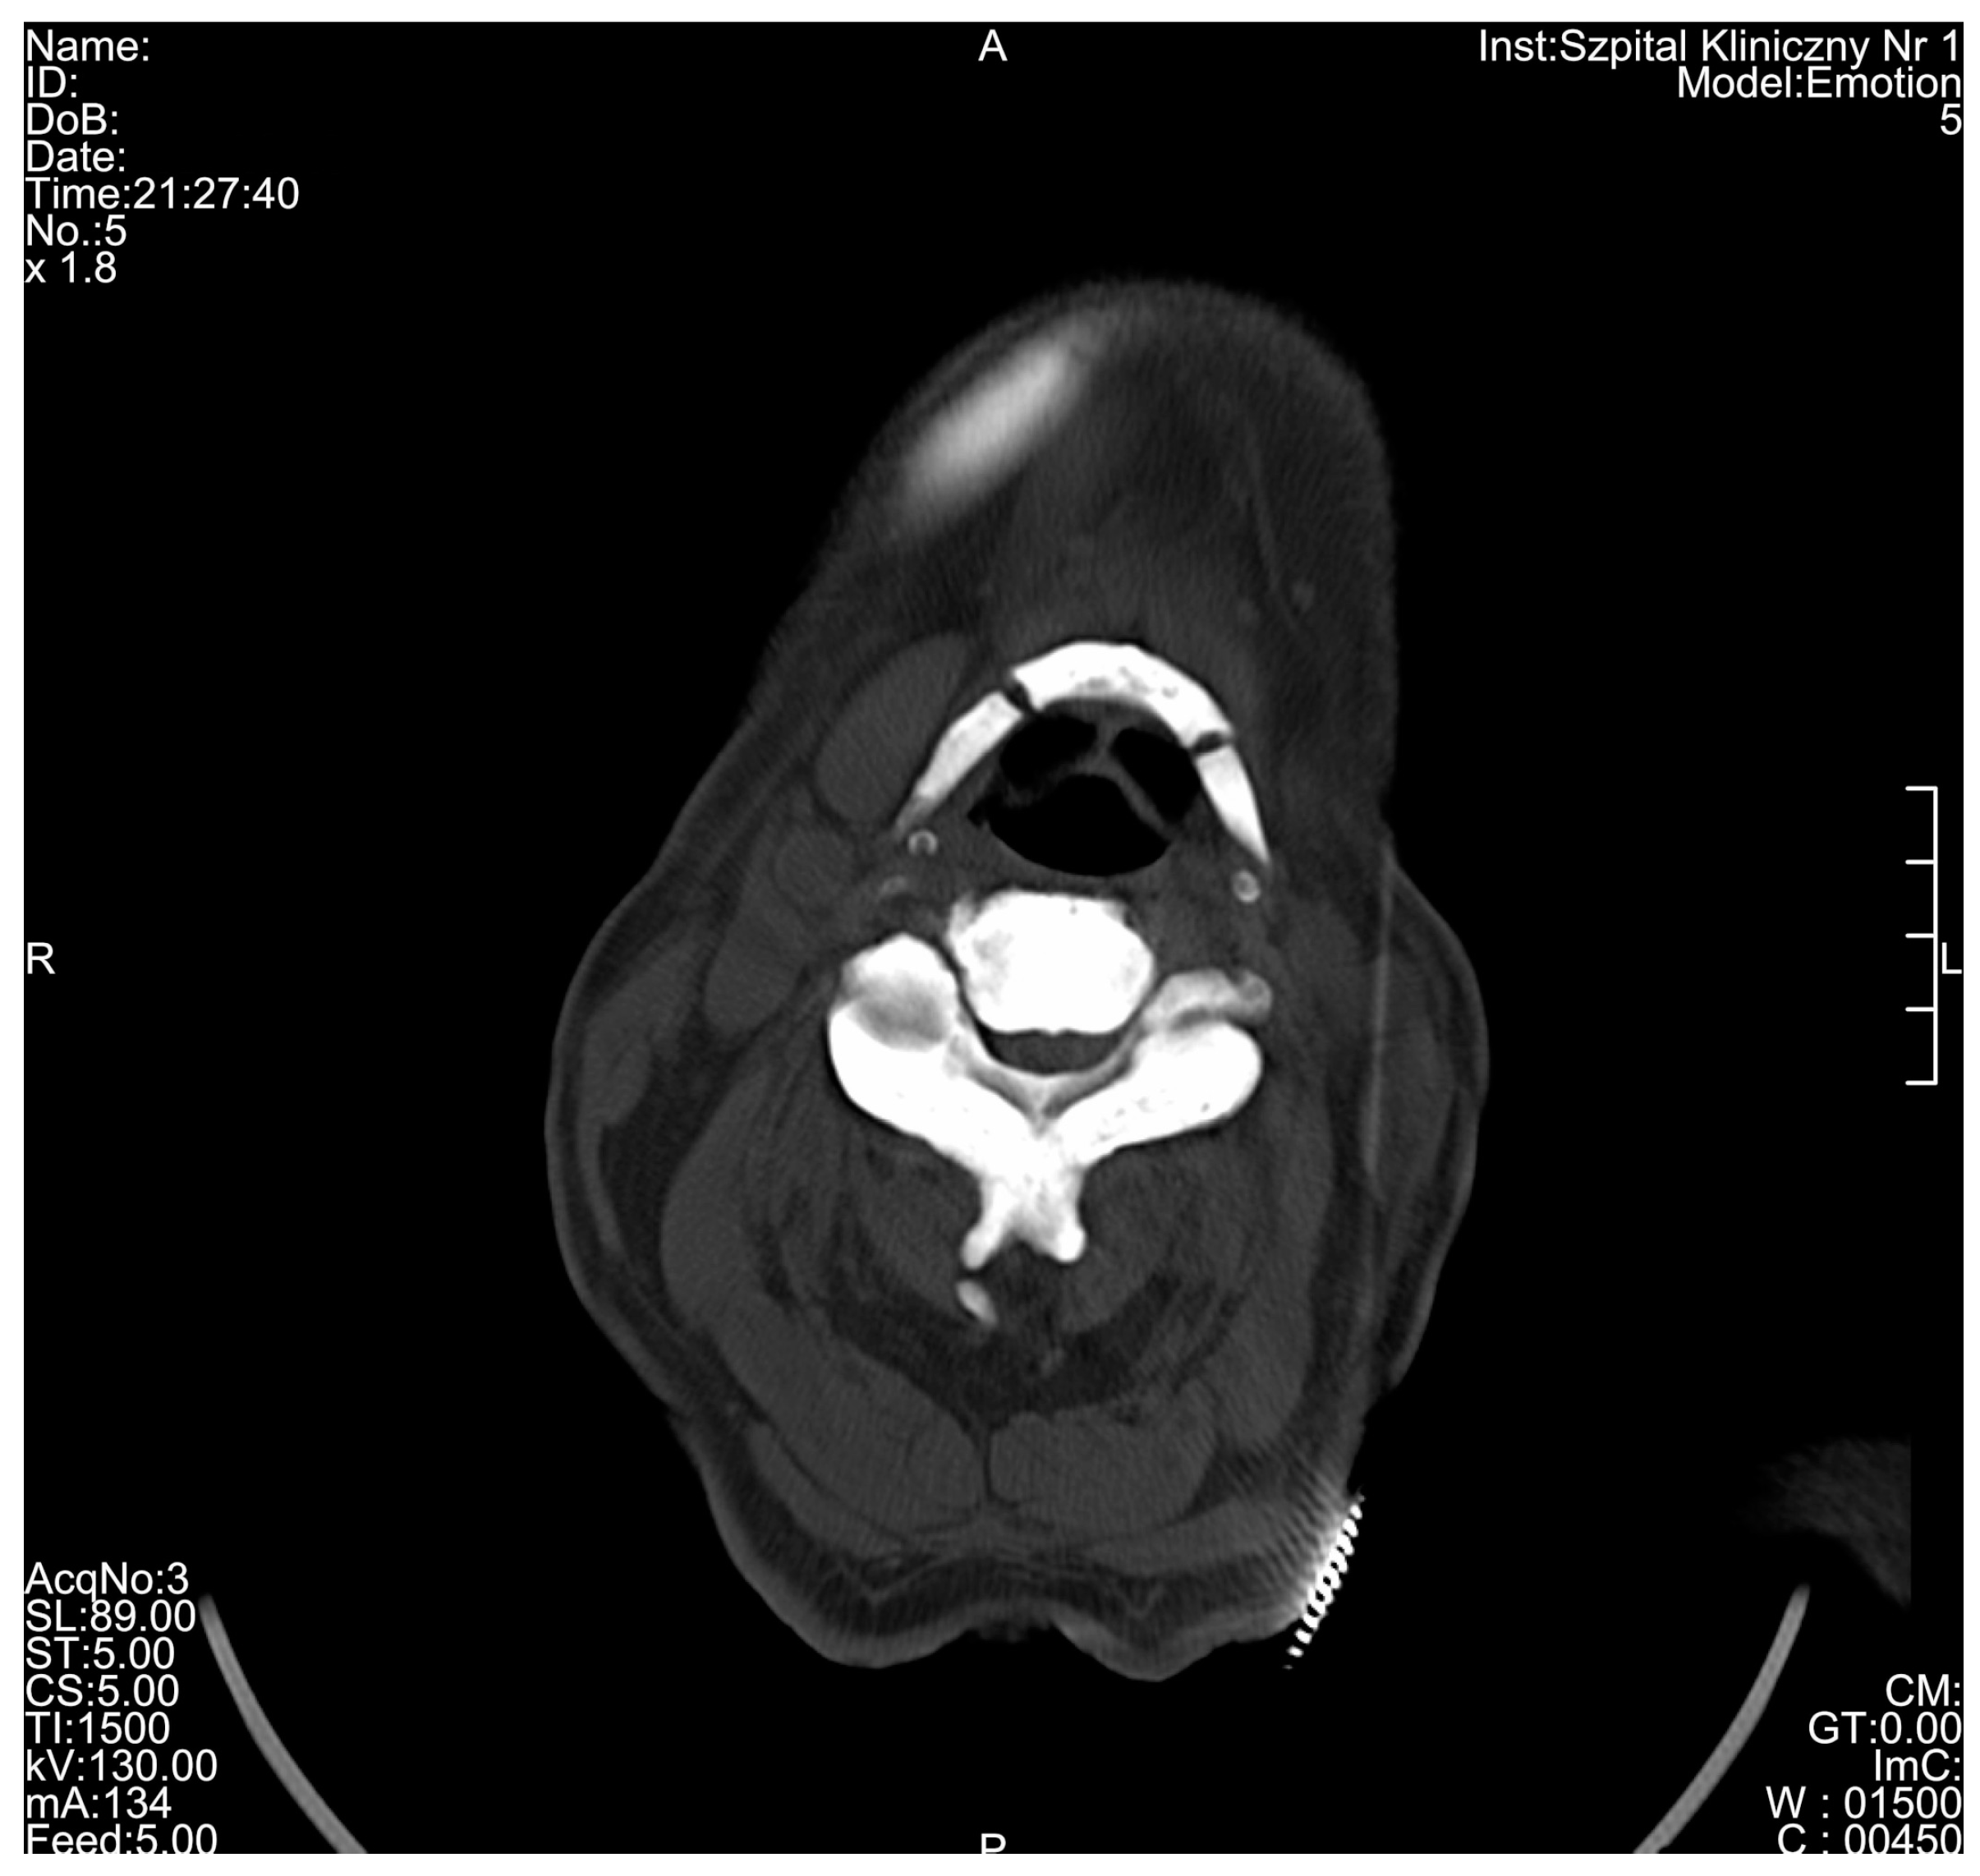

| C1 vertebra | - | - | - | - | 1.987 |

| C2 vertebra | - | - | - | - | 2.107 |

| C3 vertebra | - | - | - | - | 2.010 |

| Radiological Feature | ADO Type I | ADO Type II | ADO Type III | Presented Case |

|---|---|---|---|---|

| General osteosclerosis | + | – | + | + |

| Sandwich vertebrae (Ruger–Jersey spine) | – | + | – | + |

| Bone within bone | – | + | + | + |